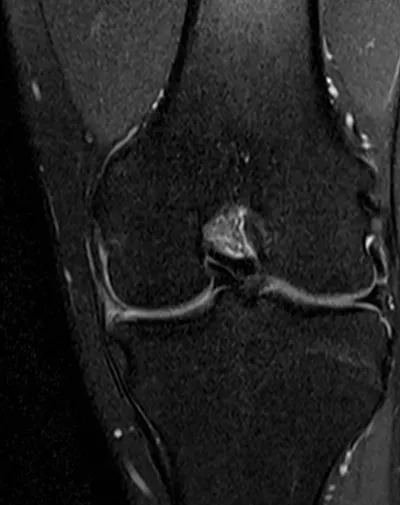

Meniscal Tear Radiology Images

Browse 4 medical images tagged with meniscal tear. This collection includes various imaging modalities for medical education and reference.

- This collection contains 4 radiology images related to meniscal tear, including various imaging modalities such as X-rays, MRIs, CT scans, and ultrasound images commonly used in medical diagnosis and education.